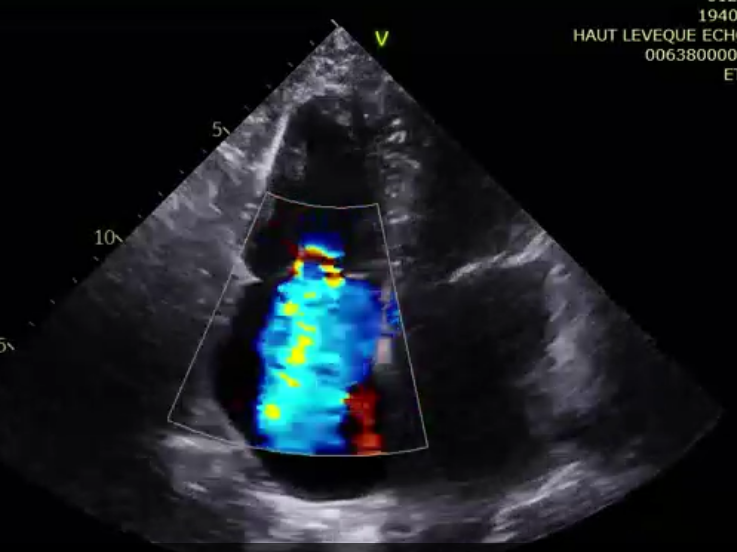

術前超聲提示極大量三尖瓣反流